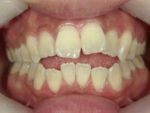

下顎前突(かがくぜんとつ)

噛み合わせたときに下の前歯が上の前歯よりも前方に突出している状態です。受け口、しゃくれ、反対咬合ともいいます。見た目上の特徴としては、下唇が上唇よりも明らかに前にでています。